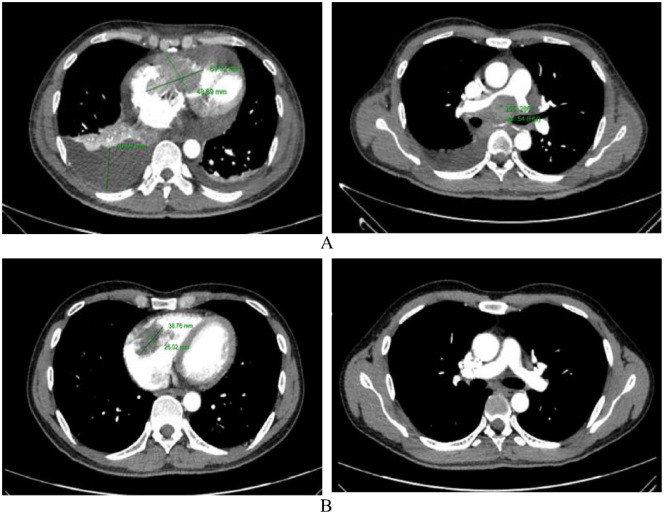

Heart tumors are sporadic. Secondary heart tumors are 30 times more common than primary ones. Depending on the location and origin of the tumor, clinical pictures vary from asymptomatic to severe manifestations such as arrhythmia, heart failure, pericardial effusion, and cardiogenic shock. We report hereby a rare case who presented with faint clinical symptoms, rapidly progressing to right heart failure within a month. Echocardiography and computed tomography of the chest revealed a tumor in the right heart chamber of 72.0 × 43.0 mm, in addition to large mediastinal lymph and left supraclavicular lymph nodes, cardiogenic shock appeared 4 days after admission. Through examination, it was suspected that this was a cardiac lymphoma. The patient was treated with 2 mg methylprednisolone per kg body weight. Symptoms of cardiogenic shock improved significantly and disappeared after 6 hours of treatment. After supraclavicular lymph node biopsy and immunohistochemistry, the final result was diagnosed as diffuse large B-cell non-Hodgkin lymphoma with large lymphoma in the right heart. The patient received chemotherapy with the R-CHOP regimen (Rituximab, Cyclophosphamide, Doxorubicin, Vincristine, and Prednisolone). Re-examination before the 5th chemotherapy cycle showed no signs of right heart failure, normal self-activity, and no dyspnea on exertion, and the tumor size in the heart on the echocardiogram was 23.8 × 19.1 mm. The report shows that a large right heart tumor with a clinical picture of cardiogenic shock in a patient with diffuse large B-cell non-Hodgkin's lymphoma was well-responded to initial treatment with methylprednisolone at a dose of 2 mg/kg body weight and R-CHOP chemotherapy.